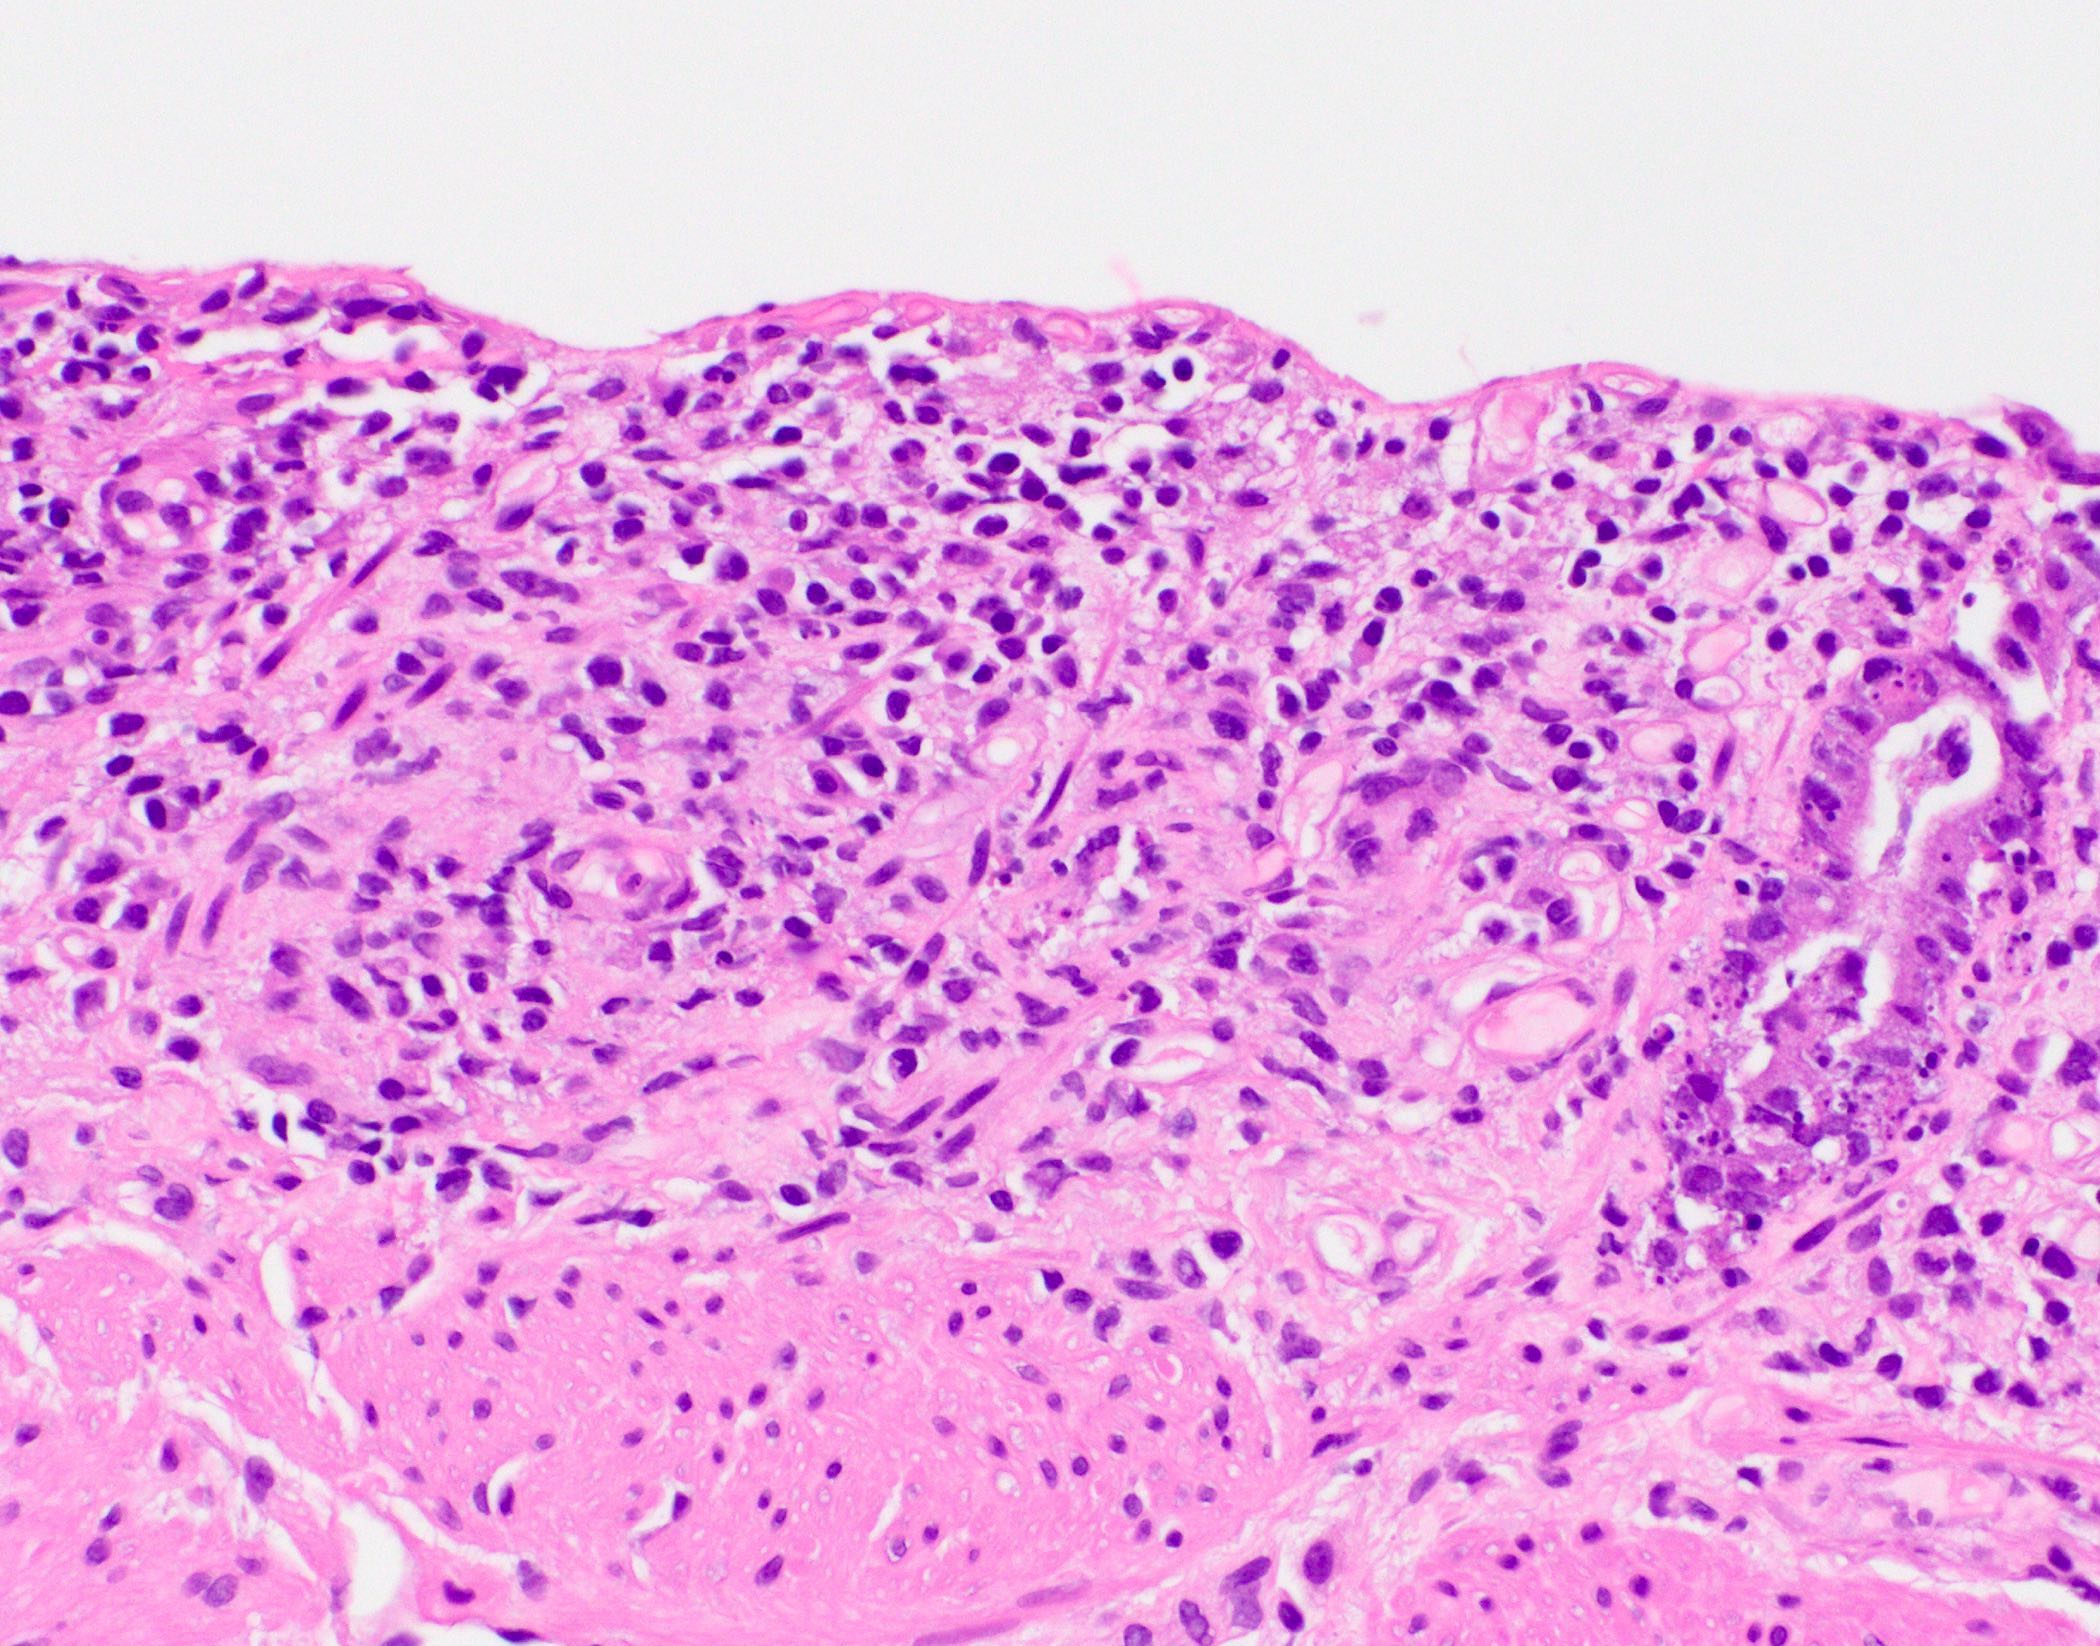

- Characteristic histologic features include crypt apoptosis, crypt dropout and ulceration (Biol Blood Marrow Transplant 2015;21:589)

- Inflammation is generally sparse

- Grade III: contiguous crypt dropout

- Grade IV: diffuse crypt dropout with ulceration

Microscopic (histologic) images